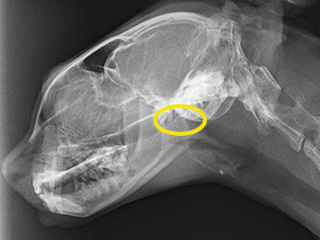

レントゲン

左:鼻の奥が狭い(鼻咽頭狭窄)

右:バルーンで広げた後

バルーンで拡張後は長年悩まされていたお鼻の症状はほぼなくなりました。

繰り返すこともある疾患のため、現在経過観察を続けています。